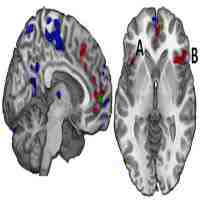

| Description | Objective: Blast-induced mild traumatic brain injuries (mTBI) commonly go undetected by computed tomography and conventional magnetic resonance imaging (MRI). This study was used to investigate functional brain network abnormalities in a group of blast-induced mTBI subjects using independent component analysis (ICA) of resting state functional MRI (fMRI) data. Methods: Twenty-eight resting state networks of 13 veterans who sustained blast-induced mTBI were compared with healthy controls across three fMRI domains: blood oxygenation level-dependent spatial maps, time course spectra and functional connectivity. Results: The mTBI group exhibited hyperactivity in the temporo-parietal junctions and hypoactivity in the left inferior temporal gyrus. Abnormal frequencies in default-mode (DMN), sensorimotor, attentional and frontal networks were detected. In addition, functional connectivity was disrupted in six network pairs: DMN–basal ganglia, attention–sensorimotor, frontal–DMN, attention–sensorimotor, attention–frontal and sensorimotor–sensorimotor. Conclusions: The results suggest white matter disruption across certain attentional networks. Additionally, given their elevated activity relative to controls', the temporo-parietal junctions of blast mTBI subjects may be compensating for diffuse axonal injury in other cortical regions. |